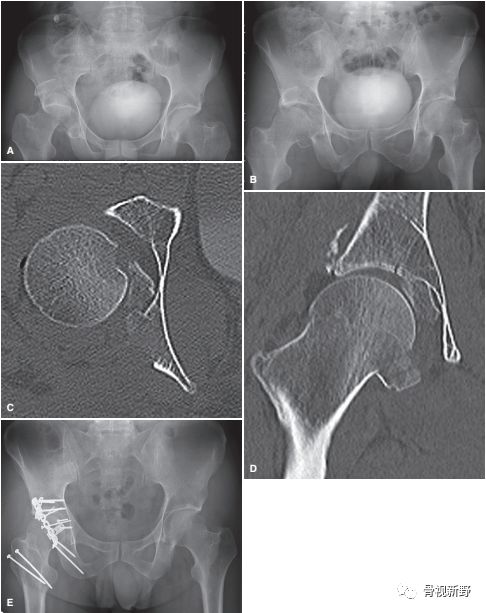

II型:对任何未解剖复位的II型骨折均应手术治疗。

Ganz入路(又称髋关节外科脱位、大转子截骨入路)

Ganz入路是常用的保髋入路之一,可360°显露髋关节。即便是Pipkin-IV型(合并髋臼骨折),也可通过梨状肌-上孖肌间隙或下孖肌-闭孔外肌间隙而显露髋臼后部;也可于大转子止点2cm以上(保护旋股内侧动脉)切断外旋短肌以显露髋臼后部。

股骨头骨块内固定应选择2.7 或3.5mm的皮质骨螺钉固定,且应作埋头处理;或用无头加压螺钉固定。

Pipkin-IV型(Ganz入路)